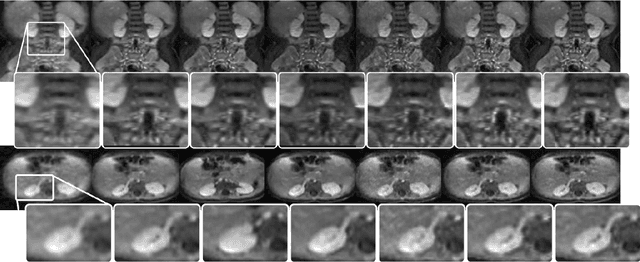

Magnetic resonance image (MRI) reconstruction is a severely ill-posed linear inverse task demanding time and resource intensive computations that can substantially trade off {\it accuracy} for {\it speed} in real-time imaging. In addition, state-of-the-art compressed sensing (CS) analytics are not cognizant of the image {\it diagnostic quality}. To cope with these challenges we put forth a novel CS framework that permeates benefits from generative adversarial networks (GAN) to train a (low-dimensional) manifold of diagnostic-quality MR images from historical patients. Leveraging a mixture of least-squares (LS) GANs and pixel-wise $\ell_1$ cost, a deep residual network with skip connections is trained as the generator that learns to remove the {\it aliasing} artifacts by projecting onto the manifold. LSGAN learns the texture details, while $\ell_1$ controls the high-frequency noise. A multilayer convolutional neural network is then jointly trained based on diagnostic quality images to discriminate the projection quality. The test phase performs feed-forward propagation over the generator network that demands a very low computational overhead. Extensive evaluations are performed on a large contrast-enhanced MR dataset of pediatric patients. In particular, images rated based on expert radiologists corroborate that GANCS retrieves high contrast images with detailed texture relative to conventional CS, and pixel-wise schemes. In addition, it offers reconstruction under a few milliseconds, two orders of magnitude faster than state-of-the-art CS-MRI schemes.